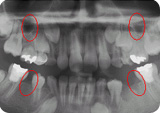

右の写真は上下左右第2小臼歯(前から

永久歯の先天欠如(もともと歯がない)は

上顎側切歯(上の前から2番目の歯)と下顎第2小臼歯(下の前から5番目の歯)に最も多く認められます。

また上顎側切歯には尖状歯(歯が円錐状の形をしている)とよばれる形態異常が時々認められます。

側切歯や第2小臼歯に先天欠如が多いのもこうした理由によるものと考えられます。

歯の形態が小さいことや先天欠如により、奥歯が前に倒れこんできたり、

前歯が片側にずれて顔の真ん中と合わなくなったりすることがあります。